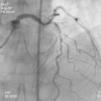

Transferido para este hospital por síndrome coronária aguda (SCA) com elevação do segmento ST da parede anterior extenso com 4 horas de evolução para angioplastia direta. A coronariografia mostrou doença coronária de três vasos associando: estenoses suboclusivas do segmento proximal (lesão culprit) e distal da descendente anterior (DA), estenose crítica do segmento médio da DA, estenoses significativas da coronária direita (CD) e da circunflexa (Cx). Submetido a intervenção na DA com implantação de três stents metálicos e bom resultado final. Durante o internamento permaneceu sem recorrência de angor, mantendo estabilidade elétrica, hemodinâmica e classe de Killip 1. Evoluiu com ondas Q associado a supradesnivelamento de ST e inversão da onda T de V1-V4, pico de troponina I > 100 ng/ml, Ckmassa 105,6 ng/ml e BNP máximo de 2.490 pg/ml.

Transferido para o Hospital de origem com o diagnostico de enfarte agudo do miocárdio (EAM) precipitado pelo uso de zolmitriptano (Figuras 1–5).